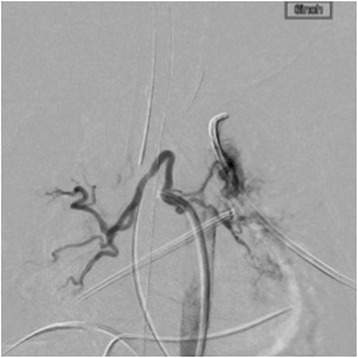

Fig. 1.

An angiography image showing two aortopulmonary arteries connecting the descending aorta and the right pulmonary artery, and one collateral artery connecting the descending aorta and the left pulmonary artery